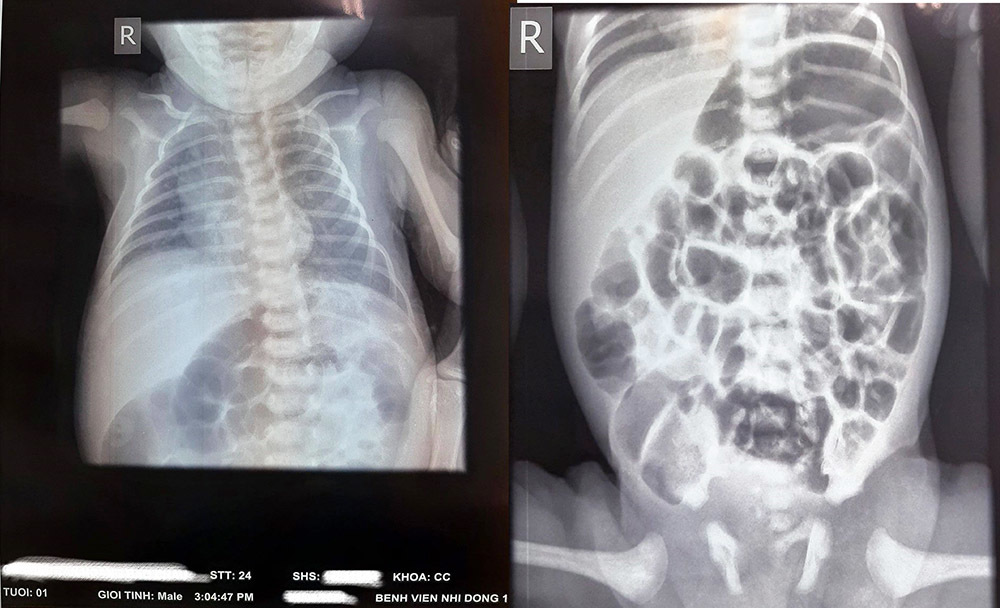

| Hình ảnh viêm ruột hoại tử của em bé mắc Covid-19. Ảnh: BSCC. |

Kết quả xét nghiệm PCR của bé dương tính với nCoV. Sau 3 ngày nhập viện, bé sốt, suy hô hấp tăng dần rồi chuyển nặng. Kết quả X-quang ghi nhận có tổn thương phổi rải rác hai bên.

Theo kết quả xét nghiệm, bé có dấu hiệu viêm ruột hoại tử. Bệnh nhi được truyền dịch nuôi ăn tĩnh mạch, sử dụng thuốc kháng sinh, kháng viêm và kháng đông.